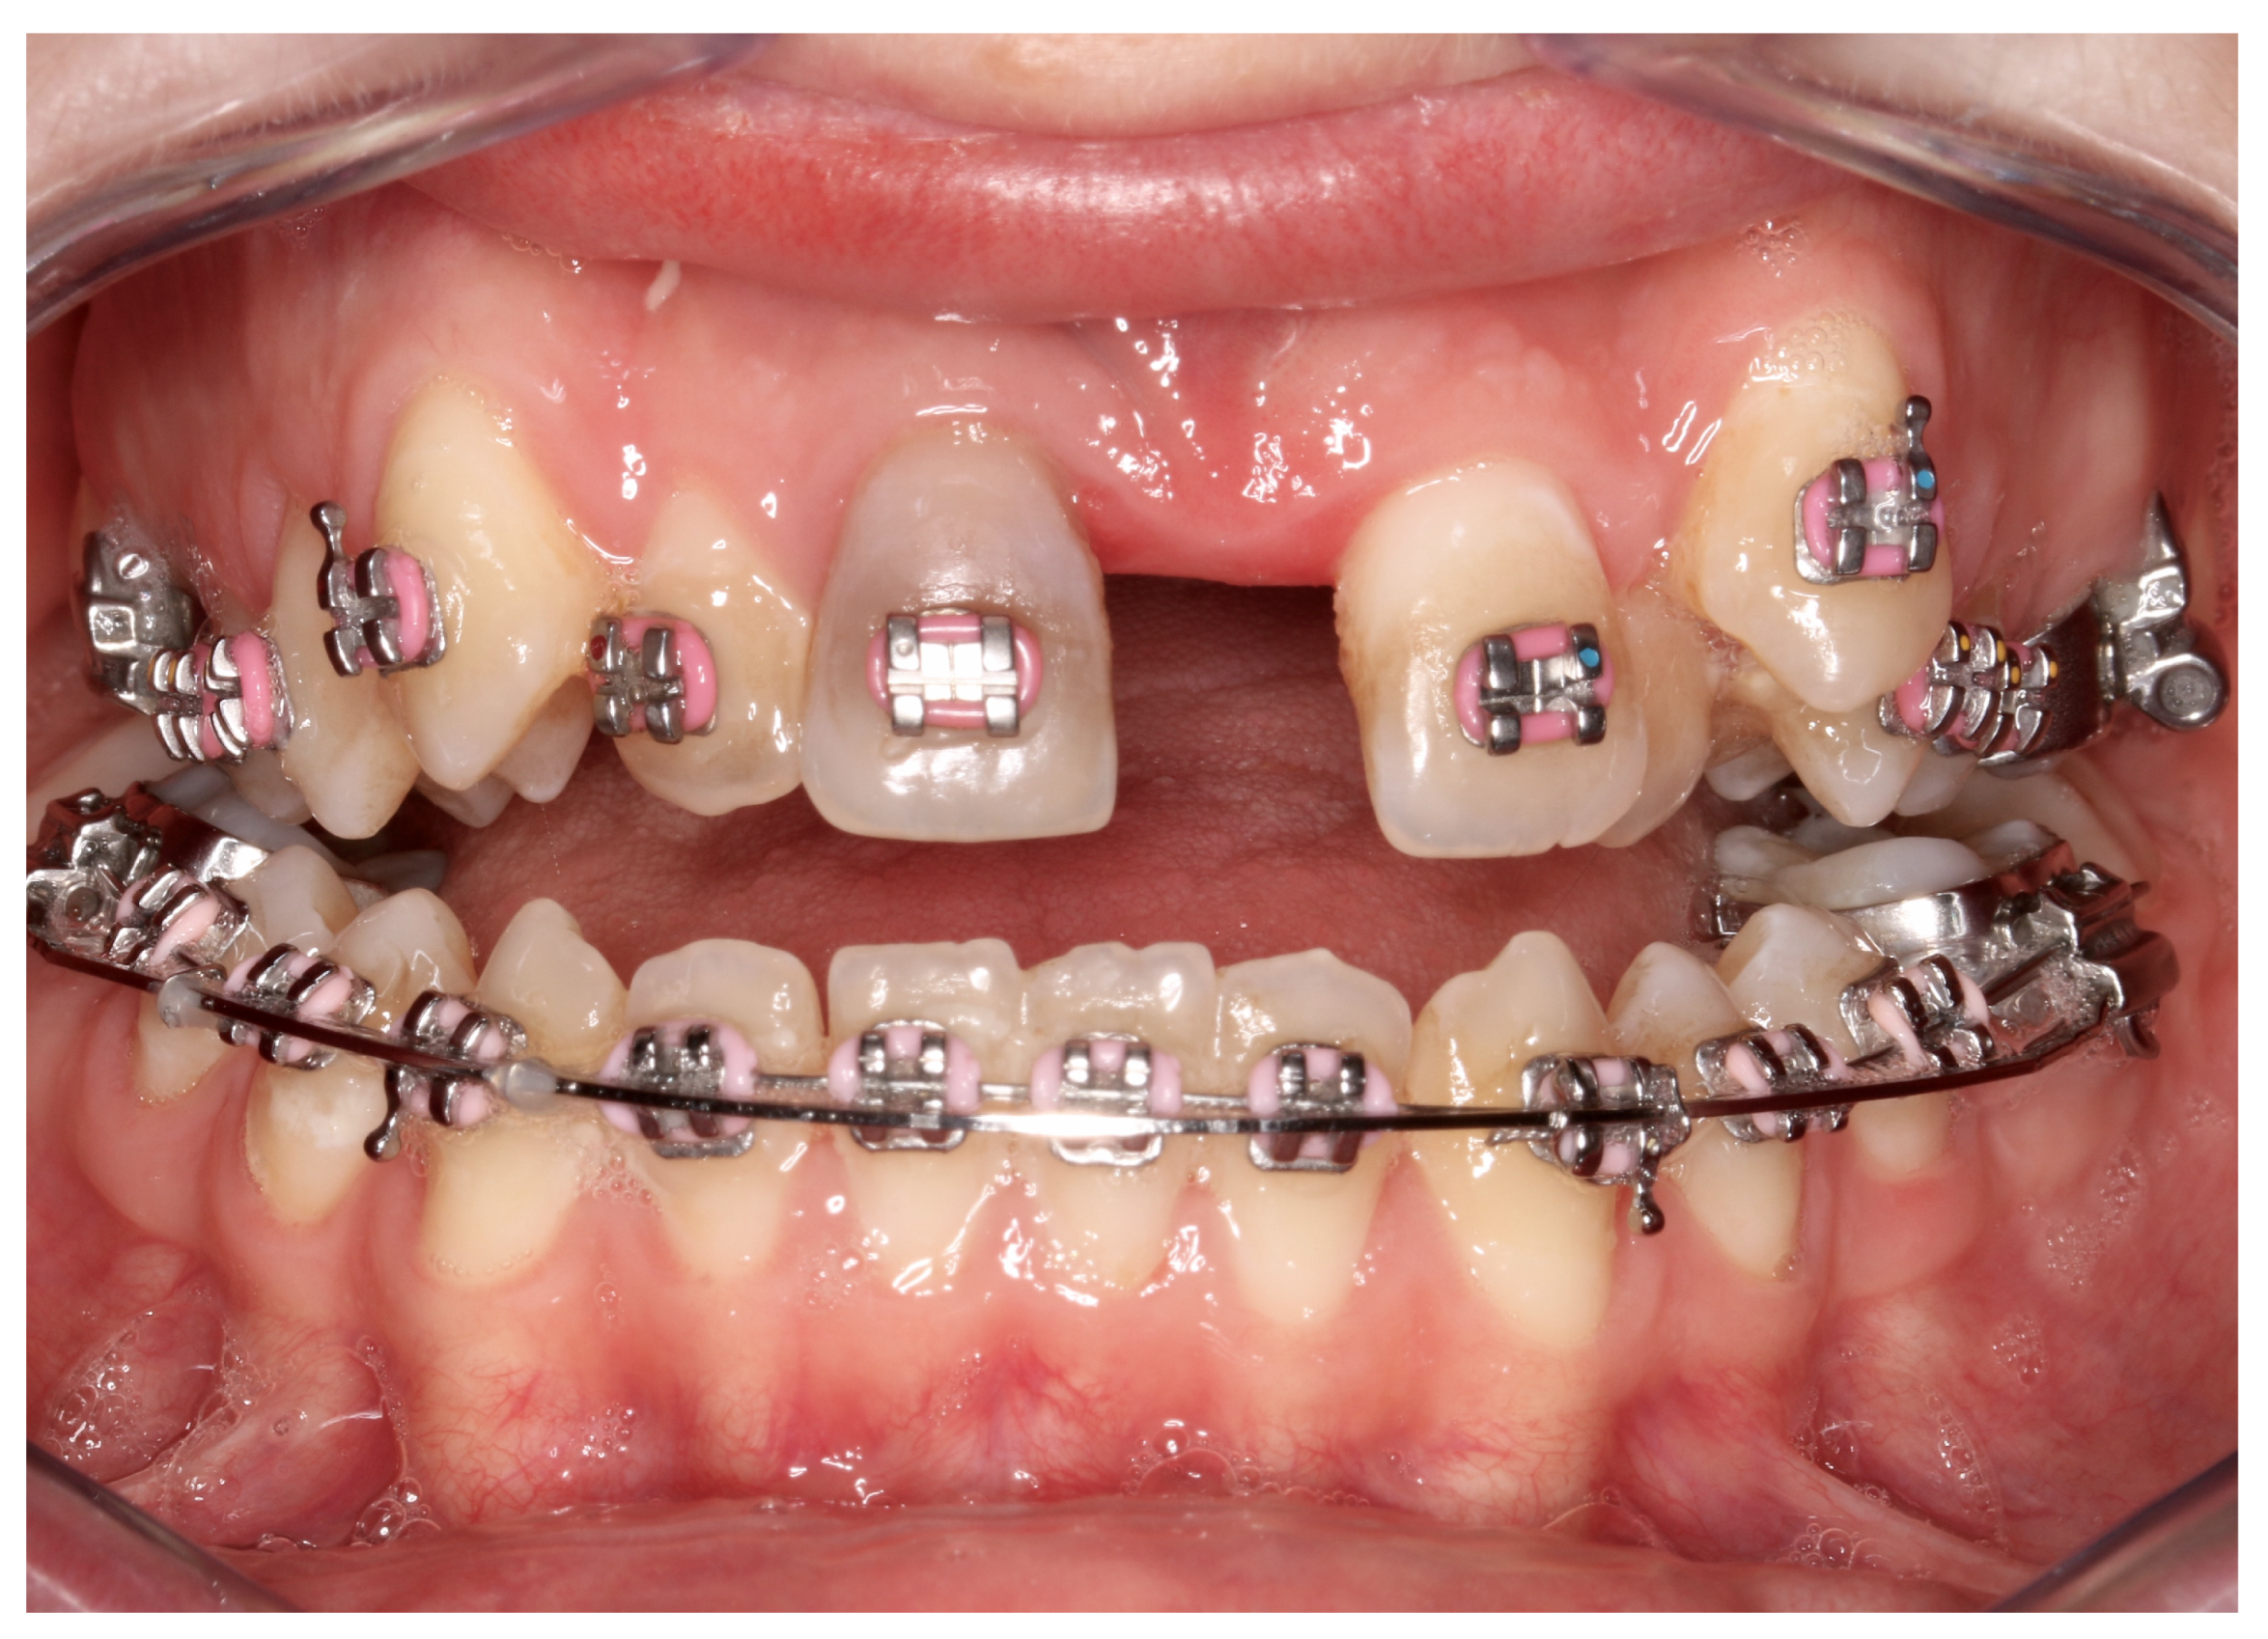

| No possibility of distraction—1 case | Maxillary incisor root resorption—2 cases |

| Palatal mucosal necrosis—2 cases | Bone loss/lack of adhesion in the distraction gap—5 cases |

| Perforation of the maxillary alveolar process caused by the distractor—1 case | Maxillary incisor necrosis—2 cases |

| Asymmetric distraction—5 cases | |

| 9 cases (4.86%) | 9 cases (4.86%) |